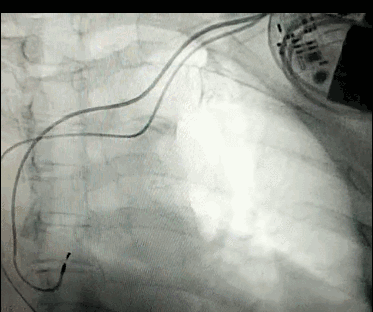

DSA是將造影劑注入需要檢查的血管中,使血管顯露原形,然后通過系統(tǒng)處理,使血管顯示更加清晰,便于醫(yī)生診斷或進(jìn)行手術(shù)。

淺析DSA的前世今生!

數(shù)字減影血管造影術(shù)是醫(yī)學(xué)影象學(xué)中,繼X線CT之后的又一項新技術(shù),也是當(dāng)前醫(yī)學(xué)影象學(xué)中具有突破性的重大進(jìn)展。?